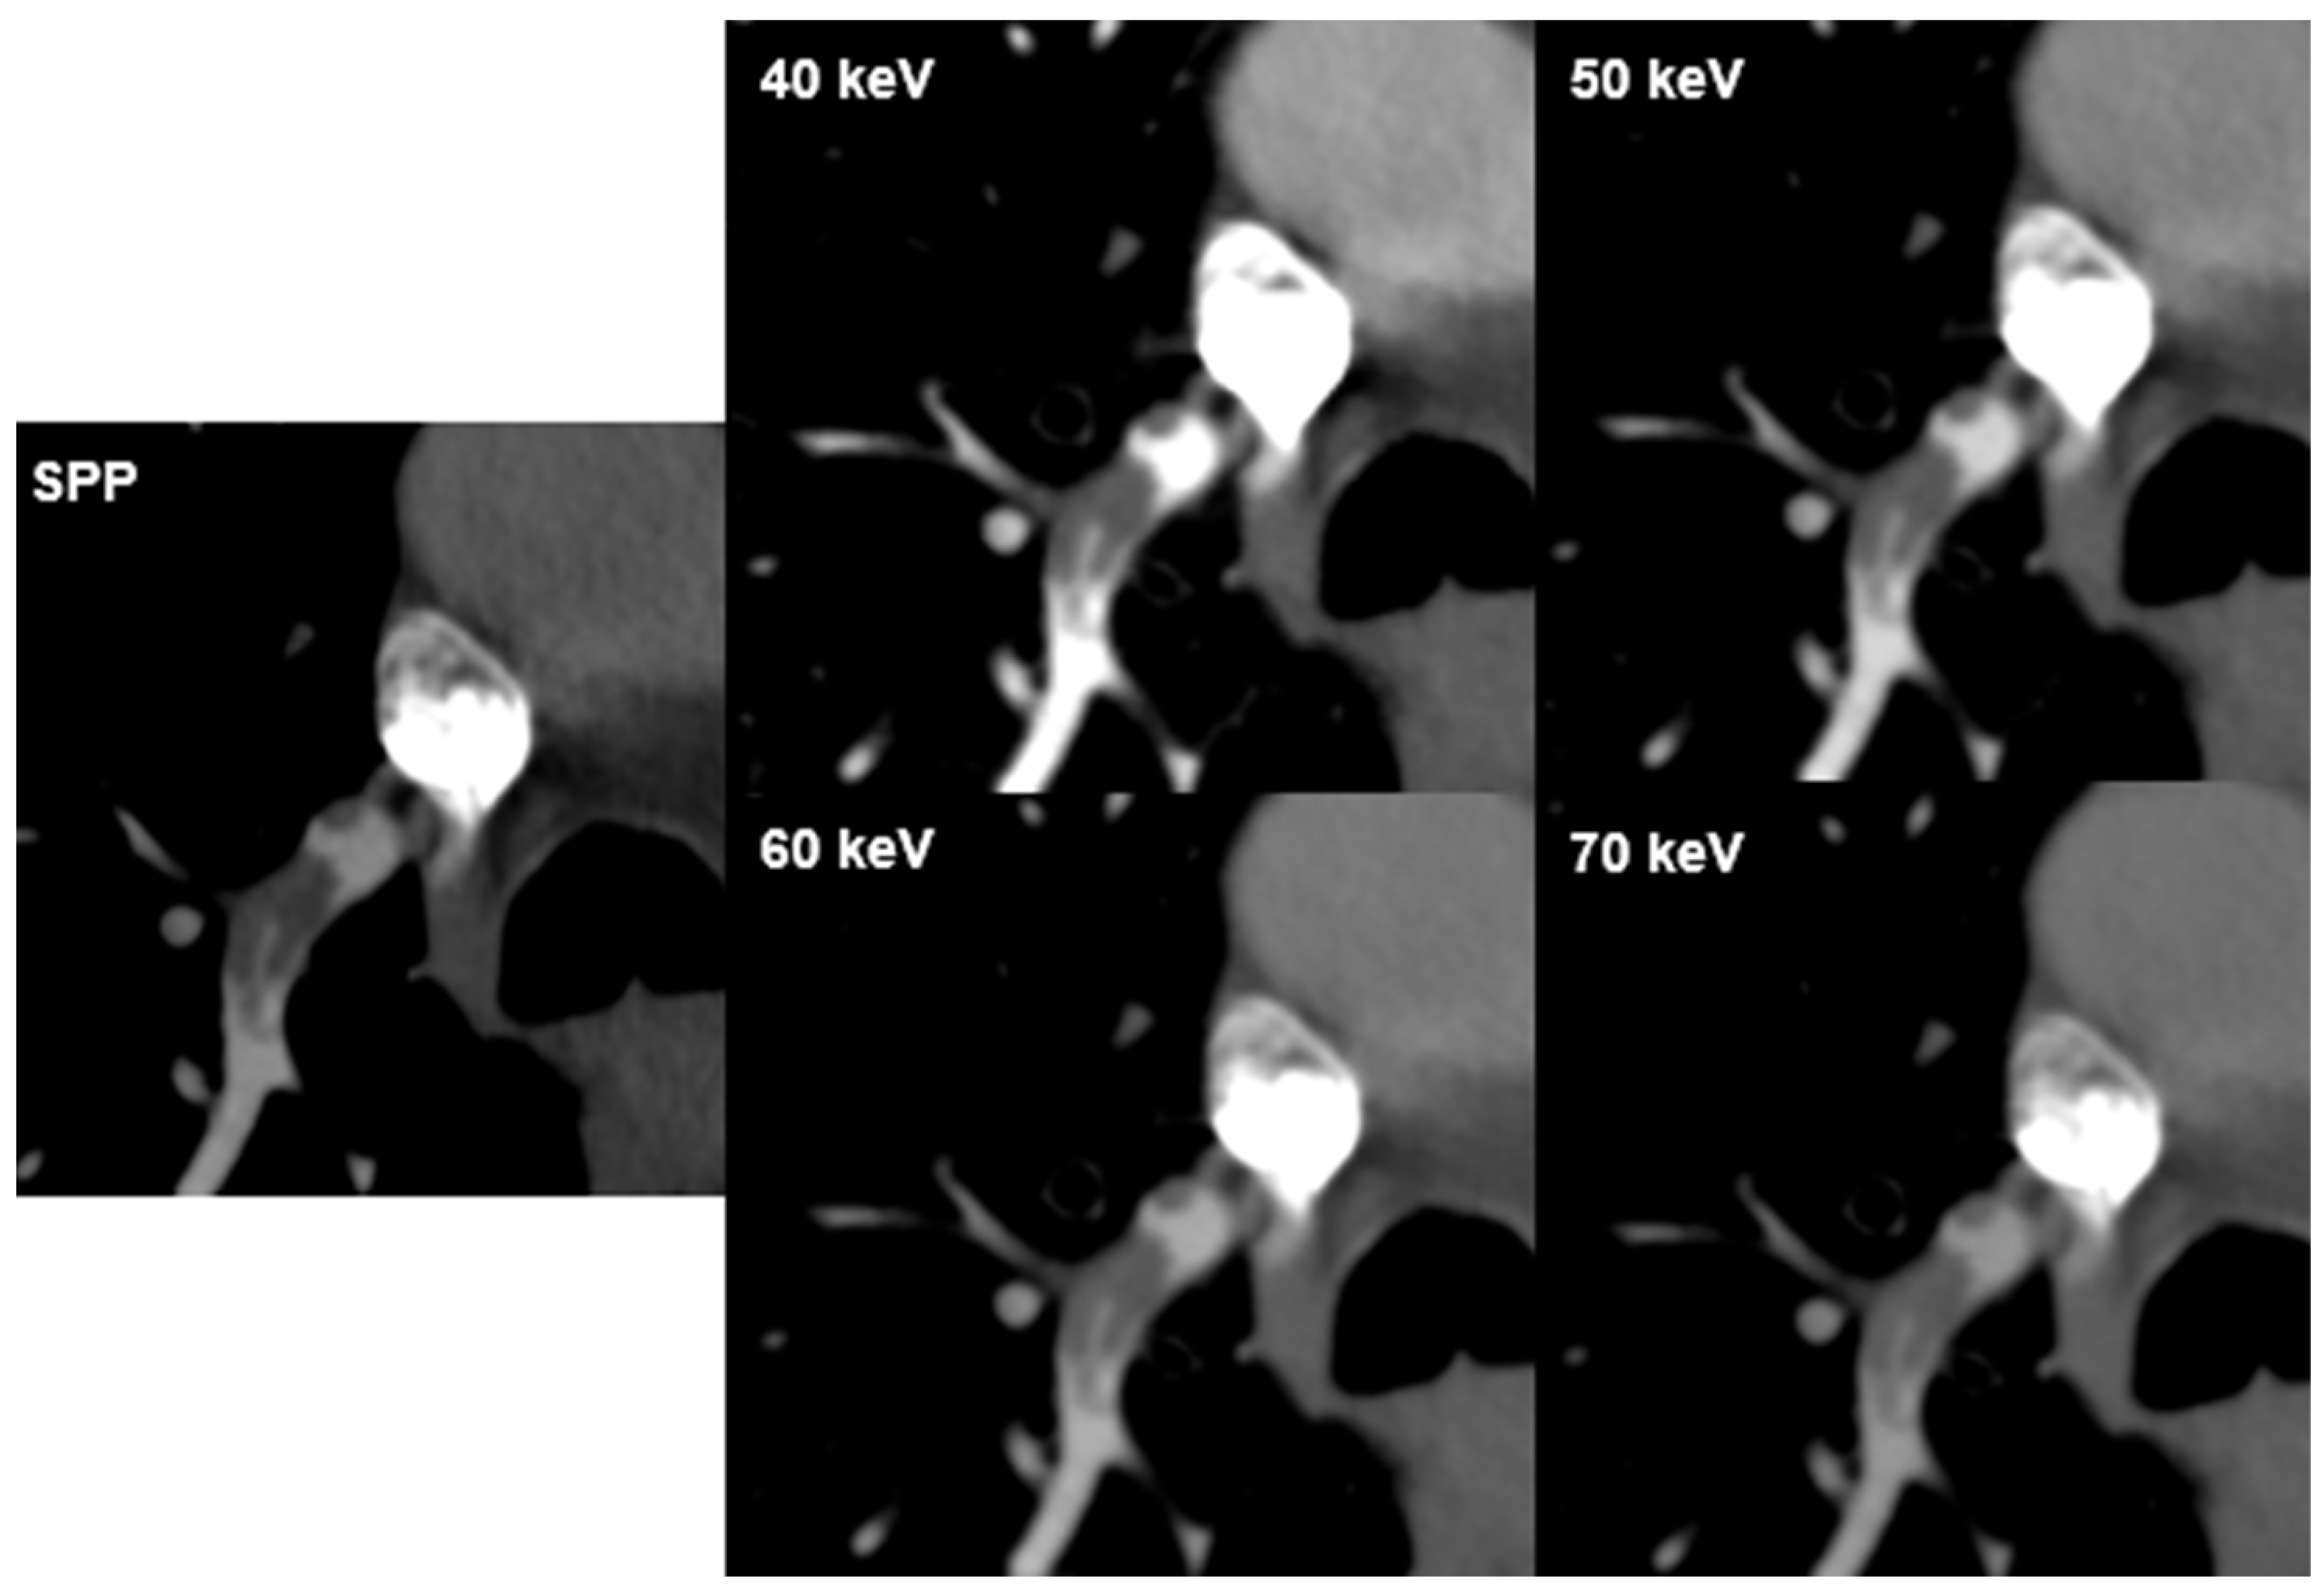

3.4. Detection of Pulmonary Embolism

Inter-reader agreement for PE visualization was fair to good (k = 0.373–0.612, p < 0.001) with good concurrence for VMI 50 keV (k = 0.612). Diagnostic confidence for the visualization of PE was rated lowest at 70 keV for both readers (mean 3.7; range 2–5 and 3.5; range 2–4; respectively). There was a negative correlation between PE visualization and VMI energies for both readers (r = −0.538 and r = −0.578, p < 0.001; respectively) (Figure 3).

Figure 3. PE visualization. CT images of a 73-year-old male patient with pulmonary embolism (PE) in a branch of the right pulmonary artery in the lower lobe at different virtual monoenergetic image (VMI) energies and the multi-energy reconstruction, including all energy spectra (SPP). Attenuation in the pulmonary artery depends on the image energy. PE is best seen at 40 keV and 50 keV.